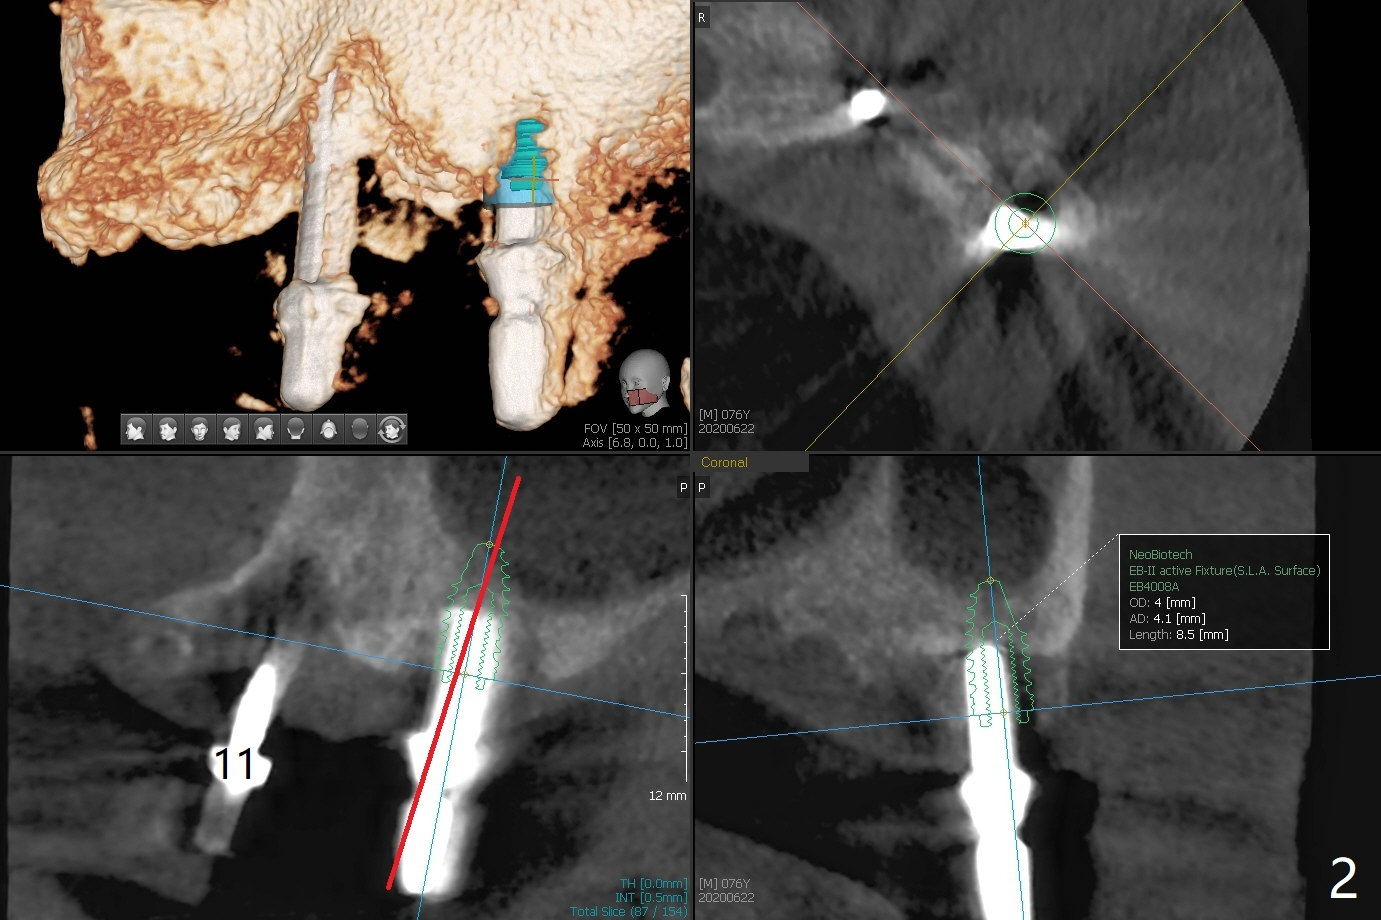

Osteotomy at #13 starts blindly (no incision or tissue punch) with bone expanders. After insertion of parallel pins, intraop CT shows that it is palatal with apparently buccal low bone density (Fig.1); the osteotomy for implant (Fig.2 green) should be shifted buccal and tilted mesial (red, parallel to #11) with incision. In contrast the position, trajectory and depth (Fig.3 <) of the initial osteotomy are acceptable at #11. The implant will be placed as it is (Fig.4). After taking a postop PA (Fig.5), the implant at #11 is placed a little deeper to make sure its slightly subcrestal placement (including distal incision at #11). Following placement of 3.5x4 and 3 mm ball abutments at #11 and 13, cortical allograft with PRF is placed around the implants, especially buccal (Fig.6,7 <). After suturing, the profile of the ball abutments is too low for RPD retention. Due to gravity other than bone density, the number of ball abutments for the maxilla should be more than for the mandible. Soft reline is done to the patient's satisfaction. The retention of the upper RPD after soft reline is satisfactory without pain 7 days postop (Fig.8). The implant at #13 is loose nearly 3 months postop (Fig.9 *: bone loss). The implant is removed while the ball abutment is untightened; the sinus floor is present. It appears that a longer and larger implant is necessary; a 4.5x10 mm dummy implant is unable to be seated deep or achieve primary stability (Fig.10). After sinus lift with 3 mm Bicon osteotome without bone graft, the dummy implant accomplishes the 2 tasks mentioned above (Fig.11). However there is no corresponding definitive implant in stock. Implant system needs to be changed; with a change in implant driver, the depth control is lost. The final implant is placed deep (Fig.12). With back up, stability is lessened; a healing screw is placed; with collagen plug, the wound is sutured (Fig.13). The wound heals 1 week postop (Fig.15). The RPD is soft relined. Retention from the ball abutment at #11 is apparently critical. The RPD and #11 implants (4 months postop) are stable, while the wound at #13 heals 1.5 months postop (Fig.15). There is space around the implant 5.5 months postop (Fig.16 *). The 5x10mm SM implant is found to be loose upon uncover and removed. After debridement, 5.3x8 mm SM and 5.5x9 mm IBS dummy implants are inserted without stability, while 6x9 mm definitive one with stability (Fig.17). Cortical allograft is placed in deficiency areas (*). The osteotomy has no roof (sinus floor), but the sinus membrane is intact. Small amount of bone graft (Fig.18 *) is placed before implantation. There appears to be bone around the new implant (Fig.19 (3D sagittal section) *).